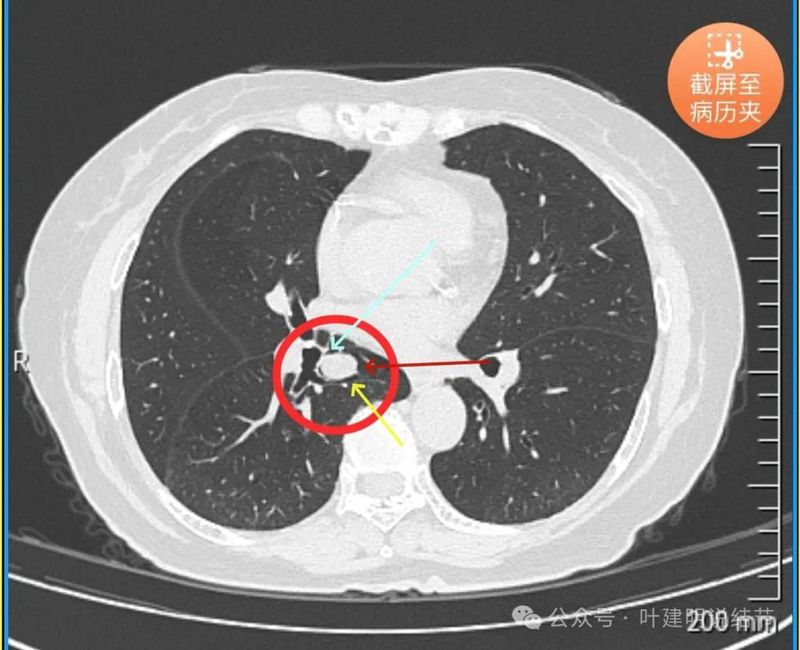

病灶密度较为均匀,对支气管是压迫后移位。表面光滑。

似乎有血管穿过。

边缘光滑,没有毛刺,膨胀性生长。

表面光滑,内部密度较均匀,边界清楚,膨胀性长。

没有侵犯邻近支气管。

边缘光滑,分叶不明显。

上图这个层面感觉病灶与肺血管之间没有明显间隙,似像侵犯或愈着的样子。

结节边缘区域与血管之间又有间隙了的。

下肺静脉水平,病灶基本没有了。